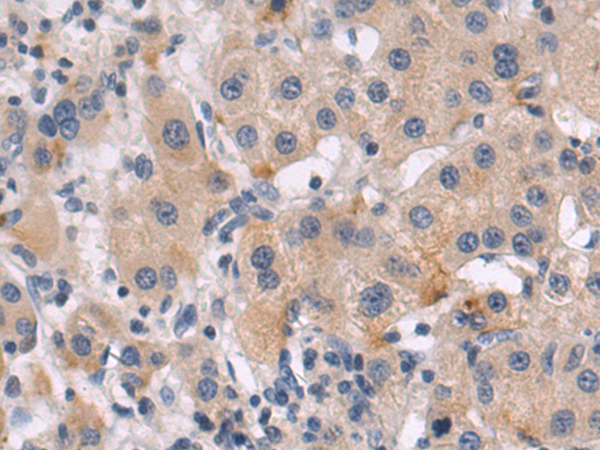

分类: 科研抗体货号: P10622别名: OI14; TRICB; TRIC-B; C9orf87; D4Ertd89e; bA219P18.1应用: WB,IHC反应种属: Human